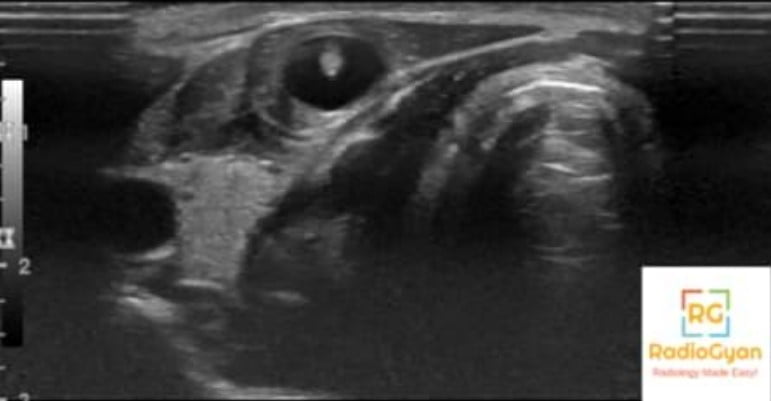

USG– Four different sonographic patterns of intramuscular cysticercosis are

- Eccentric echogenic scolex and inflammatory mass around it, as a result of the death of the larva

- Irregular cyst with very minimal fluid on one side, indicating leakage of fluid without the scolex due to escape of scolex outside the cyst or due to partial collapse of the cyst

- Irregular collection of exudative fluid within the muscle within the scolex due to chronic inflammatory reactions around the cyst

- Calcified cyst